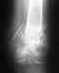

Хорошо бы сделать КТ. Будет более отчетливо видно положение сместившегося большого фрагмента суставной поверхности пяточной кости.

Операция здесь вполне уместна, после КТ это будет еще более очевидно. Вот только кто ее будет выполнять, если травматолог, как Вы пишете, всего один, и он настроен негативно.